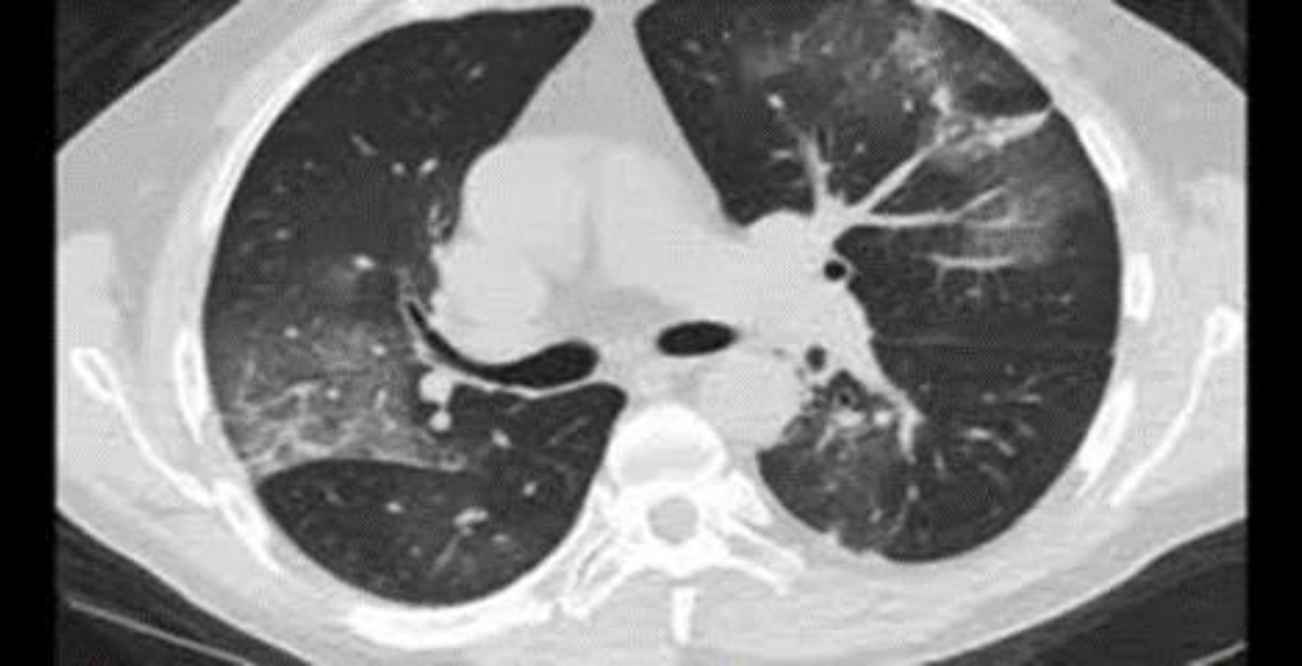

A 51-year-old man with confusion and a history of diabetes and end-stage renal disease (ESRD, who was on dialysis treatment for years) was referred to the emergency department. On arrival to the emergency department, he had a fever, respiration distress, low SpO2 level (92% with additional oxygen), and abdominal pain. High-resolution computed tomo-graphy (HRCT) was performed due to the patient’s dyspnea, which was in favor of COVID-19 (Figure 4), and two days after the PCR test, it was reported positive. Blood tests also showed high levels of amylase, INR, Partial Thromboplastin Time (PTT), lactate dehydrogenase (LDH), and thrombocytopenia (75,000/μL). In the primary complete blood cell count (CBC) test, the hemoglobin level was 10.9 mg/dL. In the lower cuts of HRCT, free air (pneumoperitoneum) was seen. The patient underwent an emergency laparo-tomy; during the operation, necrosis and perforation in three parts of the ileum with a length of 40 cm at a distance of 70 cm from the ileocecal valve were seen; after the operation, the patient’s condition became unstable that led to his death.

Fig. 4.lung involvement with COVID-19